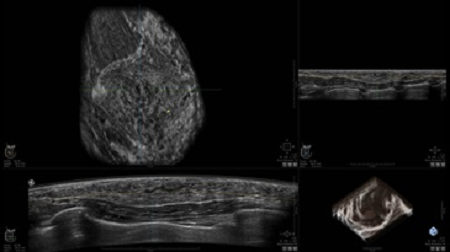

УЗИ-аппарат GE INVENIA ABUS позволяет проводить максимально операторонезависимые процедуры, что значительно снижает риск неправильной постановки диагноза и сопутствующие издержки на обработку информации. Система готовит отчет в течение 3-х минут после сканирования, это безусловное преимущество по сравнению с обычным УЗИ сканером.

• Получение объемных 3D изображений с возможностью покадрового просмотра

• Получение изображений в поперечной плоскости (в реальном времени) и в коронарной плоскости (статическая, для указания нахождения соска)

• Получение одного объемного изображения менее чем за 60 секунд

• Отображение объемных 3D ультразвуковых изображений, которые состоят из традиционных поперечных и воссозданных коронарных и сагиттальных проекций

• Возможность отображения полного 3D изображения

• Стандартизованная ориентация изображения: «толстый срез» в коронарной плоскости; поперечная; сагиттальная плоскость; радиальный и антирадиальный поворот изображения; просмотр исключительно области интереса

• Изменяемая толщина среза: 0,5 - 10,0 мм (шаг 0,5 мм)

• Срез: 0,5 - 2,0 мм (шаг 0,5 мм)